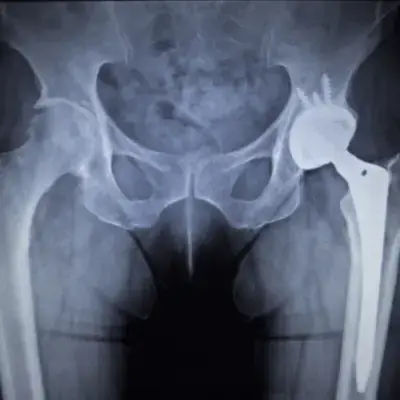

Hip Diseases and Conditions

As a distinguished orthopedic surgeon, Dr. Pramod Bhor brings a wealth of experience and exceptional skill to the treatment of various hip conditions. His expertise shines when addressing the complexities of issues such as osteoarthritis, hip dysplasia, and femoroacetabular impingement, focusing on comprehensive patient care.

What sets Dr. Bhor apart is not only his extensive knowledge but also his empathetic approach, making him a reliable choice for those in need of hip-related treatment. His ability to connect with patients on a personal level fosters a comfortable and confident environment, crucial for navigating the challenges of orthopedic health issues.

Patients looking for top-notch hip care will find in Dr. Pramod Bhor a dedicated and understanding physician, ready to offer individualized treatment plans that spotlight innovative and effective solutions.

Total Hip Replacement in Navi Mumbai